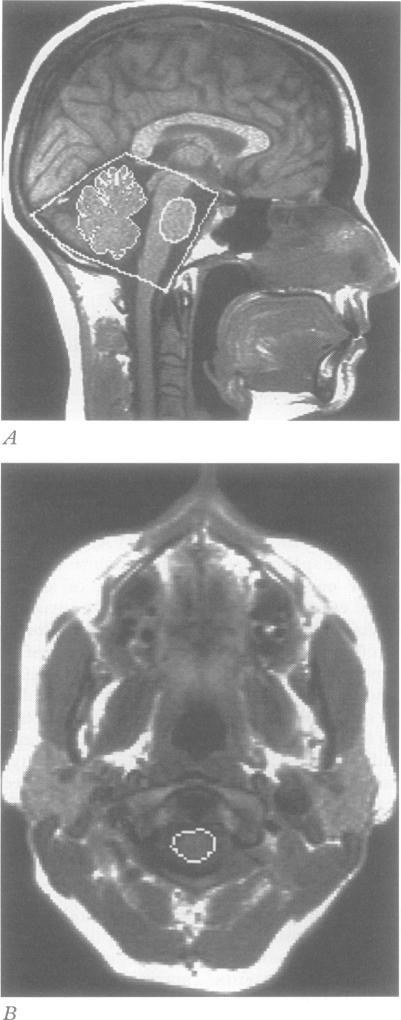

Patients with CAG trinucleotide repeat expansions on chromosome 6p (mutSCA1) and chromosome 14q (mutSCA3) had only about one half the normal concentrations of lumbar CSF homovanillic acid (HVA) whereas, 5-hydroxyindoleacetic acid (5-HIAA) concentrations were similar to those in age matched normal subjects. The HVA and 5-HIAA concentrations in clinically similar patients without mutSCA1 or mutSCA3 were normal. One year after the first study, HVA concentrations were reduced by a mean of 22% regardless of the patient's SCA mutation. Abnormalities on MRI were consistent with a spinopontine atrophy in patients with mutSCA3, spinopontocerebellar atrophy in patients with mutSCA1, and "pure" cerebellar atrophy in patients without these mutations.

6号染色体短臂(mutSCA1)和14号染色体长臂(mutSCA3)存在CAG三核苷酸重复扩增的患者,其腰椎脑脊液高香草酸(HVA)浓度仅约为正常浓度的一半,而5-羟吲哚乙酸(5-HIAA)浓度与年龄匹配的正常受试者相似。无mutSCA1或mutSCA3的临床症状相似患者的HVA和5-HIAA浓度正常。首次研究一年后,无论患者的脊髓小脑共济失调(SCA)突变情况如何,HVA浓度平均降低22%。MRI异常表现为:mutSCA3患者为脊髓脑桥萎缩,mutSCA1患者为脊髓脑桥小脑萎缩,无这些突变的患者为“单纯”小脑萎缩。